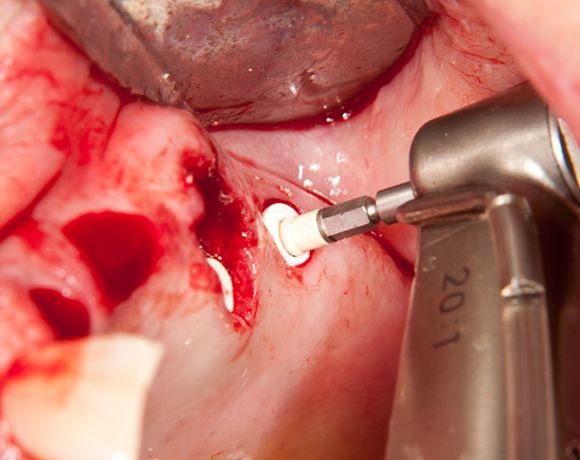

Bei dieser Patientin mussten die Zähne 22,26 und 27 aus parodontalen Gründen entfernt werden. Nach Extraktion der Zähne 22 und 26 wurden sofort in die Extraktionsalveolen die Implantate gesetzt. Zahn 27 war bereits sechs Monate zuvor extrahiert worden und die Knochenwunde gut ausgeheilt. Das geringe Knochenangebot wurde mit einem internen Sinuslift ausgeglichen. Im Bereich des Zahnes 23 wurde noch ein weiteres Implantat gesetzt. Da der Zahn 12 nicht angelegt und die Symetrie auf dieser Seite gestört war, wurden die Zähne 11 und 13 mit Teilkronen versorgt, um die Lücken zu schließen der Zahn 13 zu 12 umgebaut.